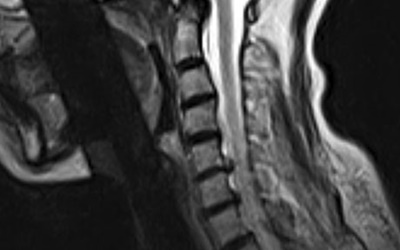

이를 의학계에서는 경추 추간판 탈출증이라고 한다고 하고요. 경추와 뼈들 사이에 존재하고 있는 물렁한 뼈조직이 있으며, 이를 디스크라고 하더라고요. 문제가 되는 것은 이 디스크가 외부로 탈출해서 신경을 압박하면서 통증이 시작되어요.